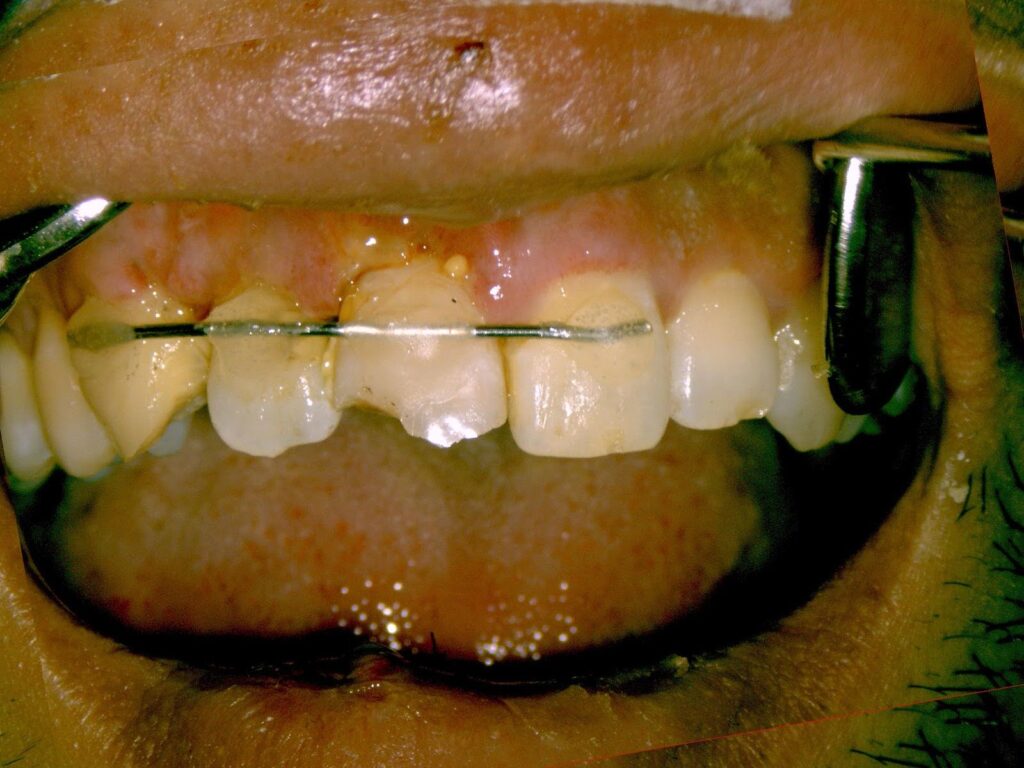

Q4 歯がめり込んだ時は?

症例)自宅前でつまづいて前のめりに転倒。前歯が骨の中に埋没。

出血多く、鏡を見て歯が無かった為、歯を失ったと意気消沈で来院

Dr.:麻酔をし、元の位置に引っ張り出して戻し、隣の歯と仮止めします。歯髄(=神経)は傷み残せない状態なので、根管治療をしました。